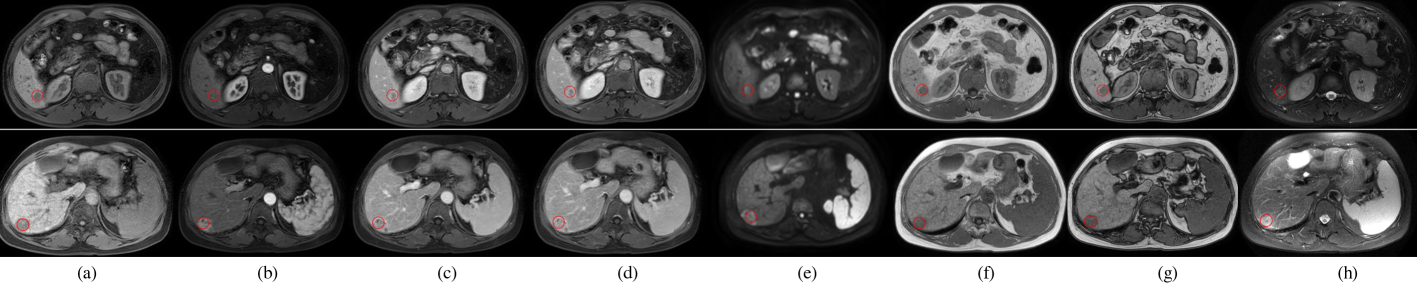

Refer to caption

Fig. 9: Visualization of different methods for rigid registration on HaN and ABD datasets. (a) Fixed images. (b) Moving images. (c) Results of ANTs. (d) Results of Elastix. (e) Results of SimpleITK. (f) Results of C2FViT. (g) Results of our UAE-M. For each image, we highlight the same two landmarks using blue and green dots. The green and blue dashed lines indicate the parallel projections of the landmarks on the fixed images.

Fig. 8: A visual comparison of lesion tracking results of SAM and UAE-S. We show two challenging cases with deformed organs and lesions, and altered contrast and image quality. Green boxes show the true lesion regions. Red circles indicate the true and tracked lesion centers. (a) and (d) are template (baseline) CT images. (b)(e) and (c)(f) are tracking results of SAM and UAE-S on the follow-up CT scans, respectively.

Table 1 displays the lesion tracking results on the DLS test set. We compared with supervised lesion tracking methods Li et al. (2019); Yan et al. (2020, 2019); Cai et al. (2021); Tang et al. (2022), registration methods Marstal et al. (2016); Balakrishnan et al. (2018); Heinrich et al. (2013), SAM Yan et al. (2022) and the improved SAM Vizitiu et al. (2023). It reveals that UAE-S outperforms all competing methods, though it does not use any task-specific supervision. Note that the organ masks used to train the semantic head contain no lesion information. The lesion tracking results produced by SAM and UAE-S were visualized in Fig. 8. It shows that the difficult cases for SAM can be effectively handled by UAE-S.

Table 2 gives the performance of landmark detection on the ChestCT dataset. Previously in Yan et al. (2022), the performance was examined exclusively on 19 test cases, focusing solely on intra-phase settings. By contrast, we conducted validation on all 94 cases, testing both intra- and inter-phase matching scenarios. It shows in Table 2 that the proposed UAE-S outperforms SAM across all settings consistently.